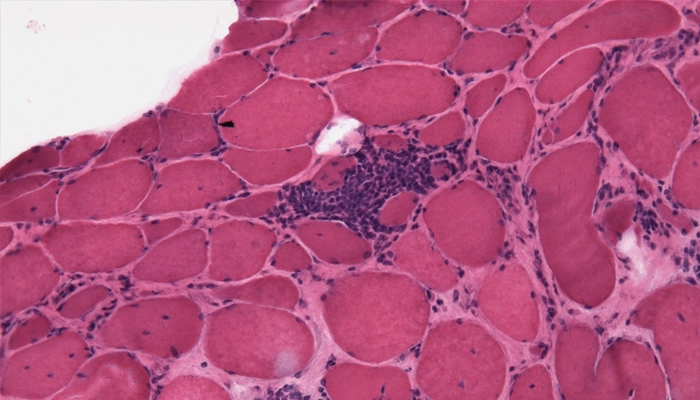

Hình ảnh sinh thiết cơ trong viêm đa cơ cho thấy thâm nhiễm tế bào viêm

Sinh thiết cơ: Đây là tiêu chuẩn vàng để xác nhận tình trạng viêm và thâm nhiễm tế bào miễn dịch.